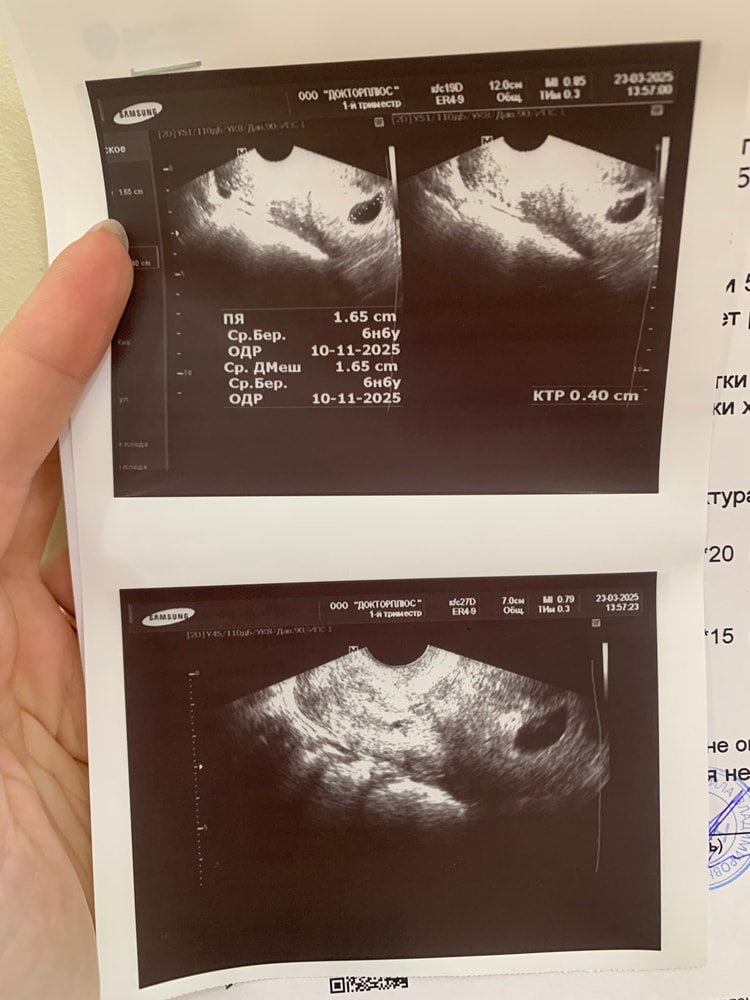

7я неделя. Второе УЗИ. Сб + 🥰